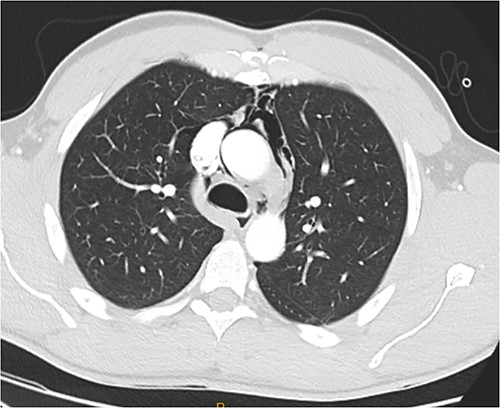

Following extubation, bilateral chest wall subcutaneous emphysema was noted extending to the neck. He also complained of central chest discomfort, without respiratory distress, oxygen desaturation or airway obstruction. Chest X-ray (CXR) revealed pneumomediastinum and surgical emphysema in the lateral chest walls bilaterally. Computed tomography (CT) of the chest, abdomen and pelvis demonstrated large volume subcutaneous emphysema bilaterally in the scrotum, abdominal and chest walls extending to the neck (see Figs 2–5). Gas was noted between the abdominal muscle layers, extraperitoneal and retroperitoneal spaces without pneumoperitoneum (see Figs 5–6). Moderate pneumomediastinum was prominent within the superior and antero-inferior mediastinum without evidence of tracheal or oesophageal injury and an associated small left pneumothorax was noted (see Figs 1–3).

CT chest and neck axial, subcutaneous emphysema extending to neck.